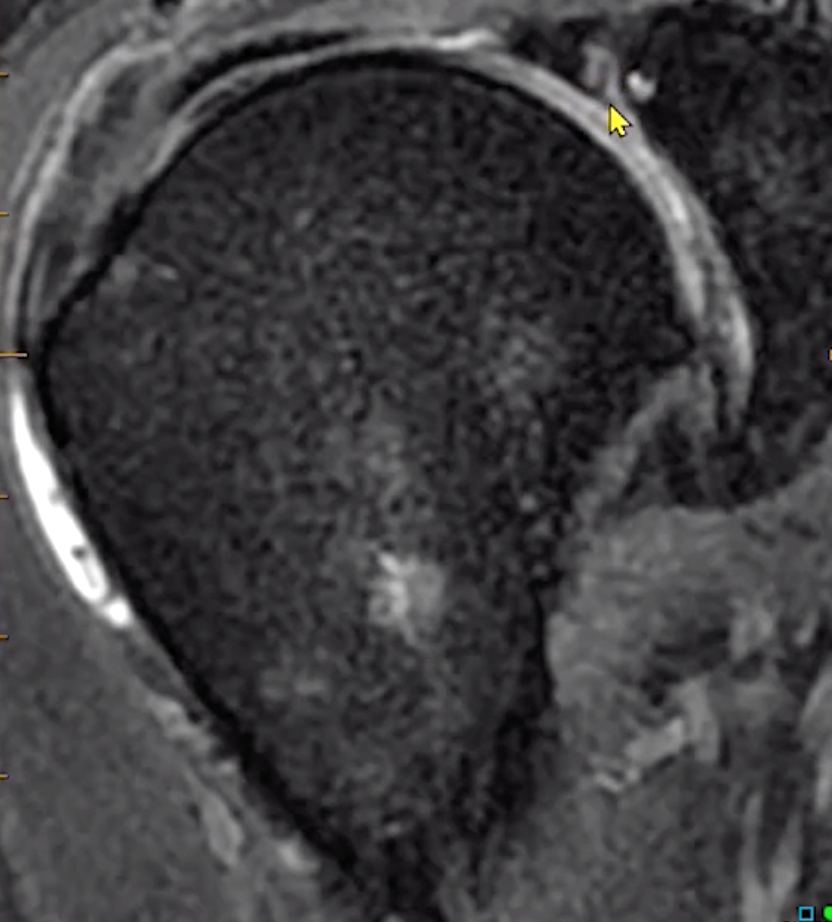

• Additional relevant items to include

• Muscle atrophy/fatty atrophy? —> helps with chronicity

• Goutallier classification